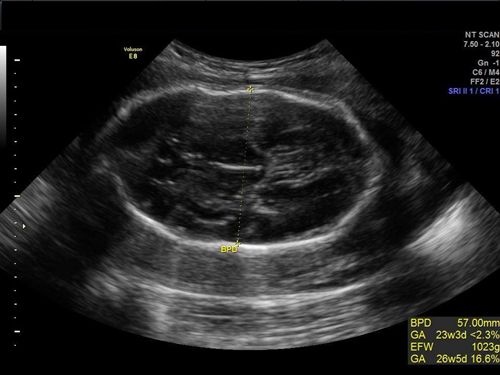

After a discrepancy between gestational age and fundal height, an ultrasound exam revealed one of the most common congenital tumors deriving from germ cells.